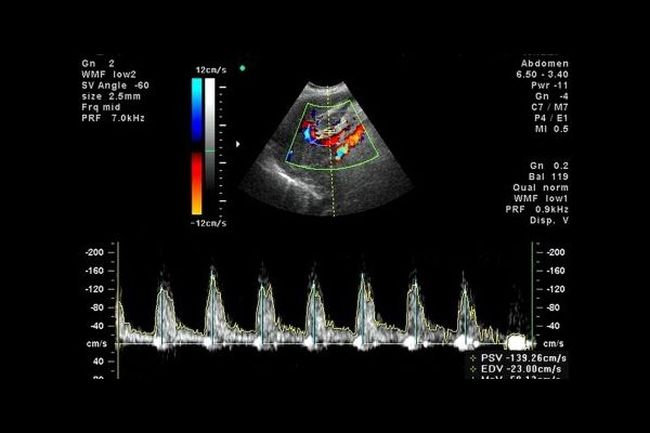

Данное исследование несколько отличается от традиционных УЗД. Дело в том, что датчик расположенный в допплеровском аппарате реагирует на какое-либо движение. Если происходит исследование организма беременной женщины, то он реагирует на движение крови, а именно эритроцитов. Допплеровский спектр отображается на экране монитора и благодаря ему врач судит о состоянии гемодинамики.

- Триплексное сканирование (ЦДК) – выполняет те же функции, но еще и отображает цветную картинку на экране устройства. Благодаря этому специалист может видеть более полную картину состояния системы кровообращения эмбриона и беременной. А также дифференцировать причину возникновения той или иной патологии.

Гинеколог начинает проведение процедуры с внимательного исследования артериального кровотока сообщающих матку с плацентой. При чем обязательно следует проводить изучение и той, и другой стороны кровообращения. Все потому что нарушения в 2/3 беременностей, которые отягощены гестозом, врач отмечает только лишь с одной стороны. Для проведения анализа скорости кровотока в сосудах матки используется индекс резистентности. ИР можно рассчитать по формуле ИР=(С — Д)/С. В этой формуле С является максимальной систолической скоростью кровообращения, Д – конечная диастолическая скорость кровообращения. Систола соответствует сокращения желудочков сердца, а диастола – это промежуток расслабления. По этим показателям проходит анализ кровообращения и его динамики. Чтобы получить среднее значение ИР нужно провести несколько определений сердечного цикла. Для расшифровки значений существует специальная таблица.

После того как гинеколог провел изучение артерий матки, далее происходит исследование сосудов плода и пуповины. Это позволяет оценить компенсаторные механизмы, а также степень нарушений кровообращения. Для того чтобы провести исследование средней мозговой артерии должно делаться ЦДК.

Помимо ИР для оценки кровообращения между плацентой и плодом используется СДО и ПИ. СДО является соотношением систолы и диастолы, а ПИ – это пульсационный индекс, который рассчитывается по формуле ПИ=(С-Д)/М. М считается средним значением скорость кровотока.